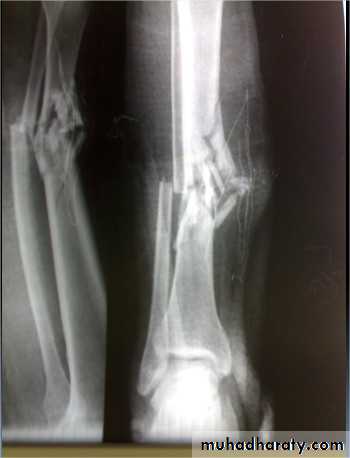

Comminuted fractures of the tibial plafond (Pilon fracture)

Severe axial compression of the ankle (FFH).

Shattering of ankle joint surface.

Swelling and blistering; treated by elevation and calcaneal traction.

Secondary Osteoarthritis is common.